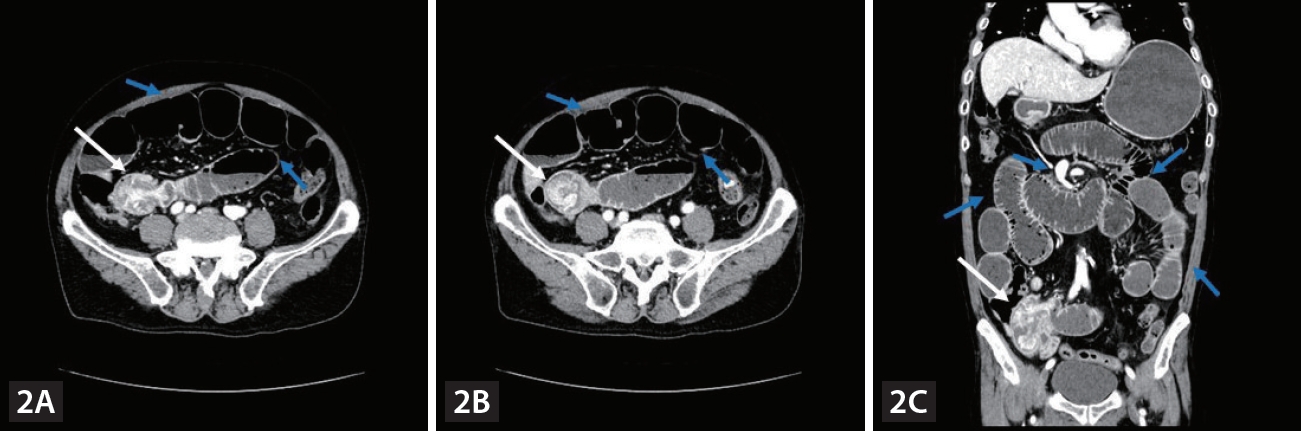

Computed tomography (CT) imaging. (A, B) Contrast-enhanced CT showed polypoid enhancing masses (white arrow) in the distal ileum.

A 75-year-old man with chronic hepatitis B was diagnosed with pulmonary metastases from hepatocellular carcinoma (HCC) and was treated in order with sorafenib, regorafenib and nivolumab. However, nivolumab treatment was discontinued after the 13th administration because of poor general condition. After 2 years of conservative management, follow-up computed tomography (CT) showed no definite viable tumor in the liver and no pulmonary metastatic lesions and tumor markers were not elevated. However, iron deficiency anemia (IDA) was observed. Fecal occult blood test was negative. Although further esophagogastroduodenoscopy and colonoscopy were performed, no definite cause of the gastrointestinal (GI) bleeding was identified. While prescribing iron supplements, we performed follow-up examinations. Six months later, follow-up abdominal CT showed polypoid enhancing masses in the distal ileum (Fig. 1). There was no viable intrahepatic lesion. Laboratory results showed IDA and elevated protein induced by vitamin K absence or antagonist-II level (90.8 mAU/mL). The patient denied melena. Polypoid lesions were not detected on colonoscopy and video capsule endoscopy. Three months later, the patient visited the emergency room complaining of nausea, vomiting and abdominal pain. The AFP level was 1.9 ng/mL and PIVKA-II level was 98.7 mAU/mL. An abdominal CT scan showed polypoid enhancing masses in the distal ileum at intussuscipiens, suggesting intussusception of the ileum with a lead point (Fig. 2). Segmental small bowel resection and endto end anastomosis were performed. The histological findings were consistent with those of metastatic HCC (Fig. 3). Small bowel intussusception in adult due to metastasis from HCC is extremely rare. To date, only four cases have been reported. Two cases were diagnosed with HCC metastasis to the small bowel manifesting as intussusception, and one case was diagnosed with double-balloon enteroscopy, and the other case was diagnosed with 11C-Acetate PET/CT. Our case was a small bowel metastasis of HCC manifested as obscure-occult GI bleeding, resulting in intussusception. To our knowledge, this is the first report of HCC metastasis to the small bowel manifested as obscure-occult GI bleeding. Even if HCC metastasis to the small bowel is rare, if HCC patients exhibit obscure-occult GI bleeding symptoms, it should be considered.